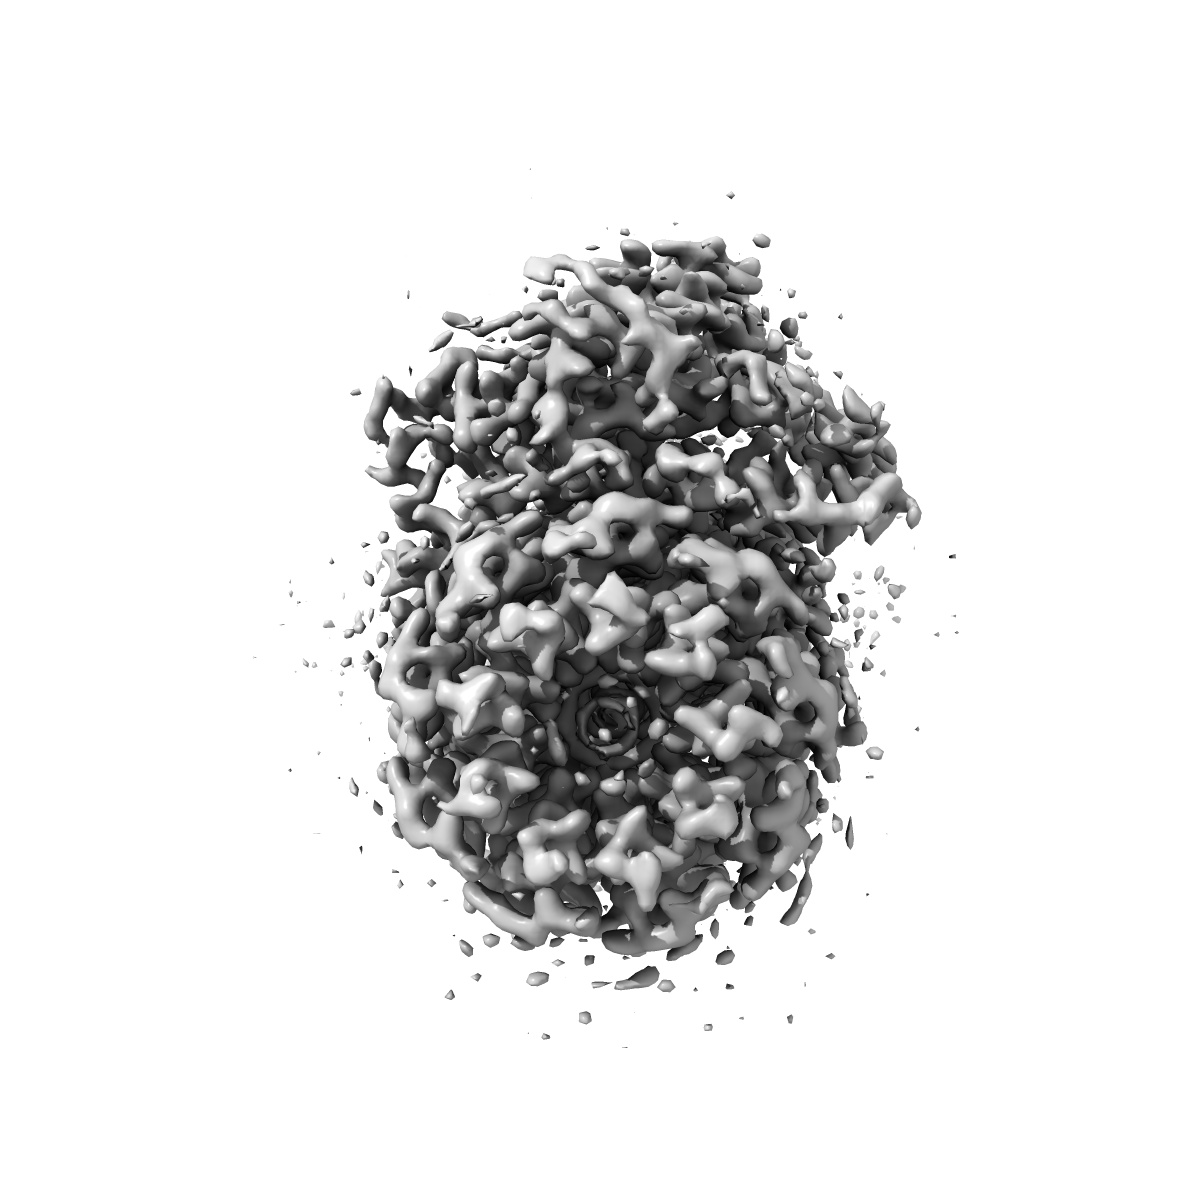

Cryo-EM structure of Mycobacterium tuberculosis ATP synthase Fo in complex with bedaquiline(BDQ)

Single-particle2.85 Å

Sample: Mycobacterium tuberculosis ATP synthase Fo with bedaquiline(BDQ)